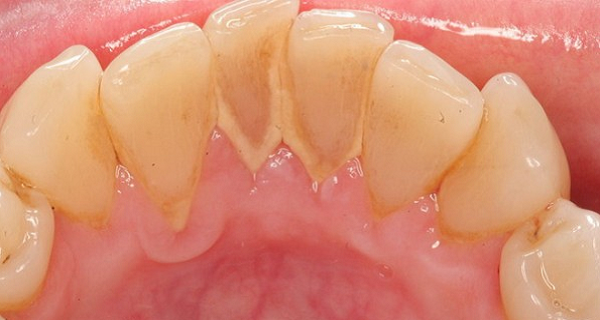

Old  Default Bí quyết tự nhiên giúp bạn làm sạch CAO RĂNG hiệu quả ngay tại nhà

Khi nói đến việc làm sạch cao răng, bạn thường cho rằng chỉ có nha sĩ mới có thể làm được điều này?

Tuy nhiên, có rất nhiều công thức nhiên thông giúp bạn làm sạch cao răng hiệu quả ngay tại nhà.